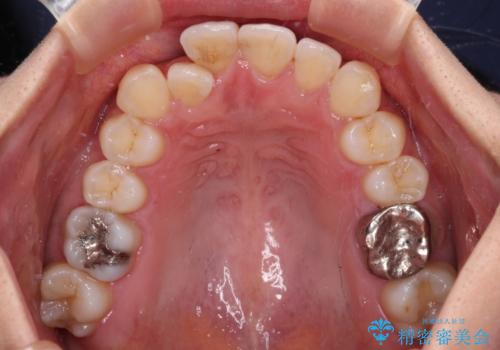

- 前歯のクロスバイトと口元の膨らんだ横顔の印象を気にして来院された患者様です。

しかしながら。そのまま叢生を解消すると横顔が突出した印象になる可能性が高かったため、上下左右の小臼歯4本を抜歯して、ワイヤー装置にて矯正治療を行うこととしました。

上下左右の第一小臼歯4本を抜歯して治療を行うことがセオリーでしたが、左下は第二小臼歯が銀歯であったため、イレギュラーではありますが、そちらを抜歯しました。

その影響で治療期間は長くなりましたが、処置していない歯を保存することができました。